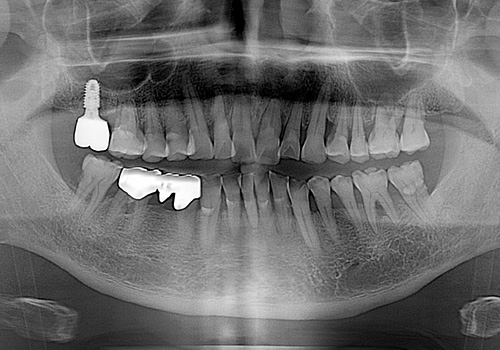

김○영님 임플란트 식립 전

2019년 2월

김○영님 임플란트 식립 후

2019년 11월 -